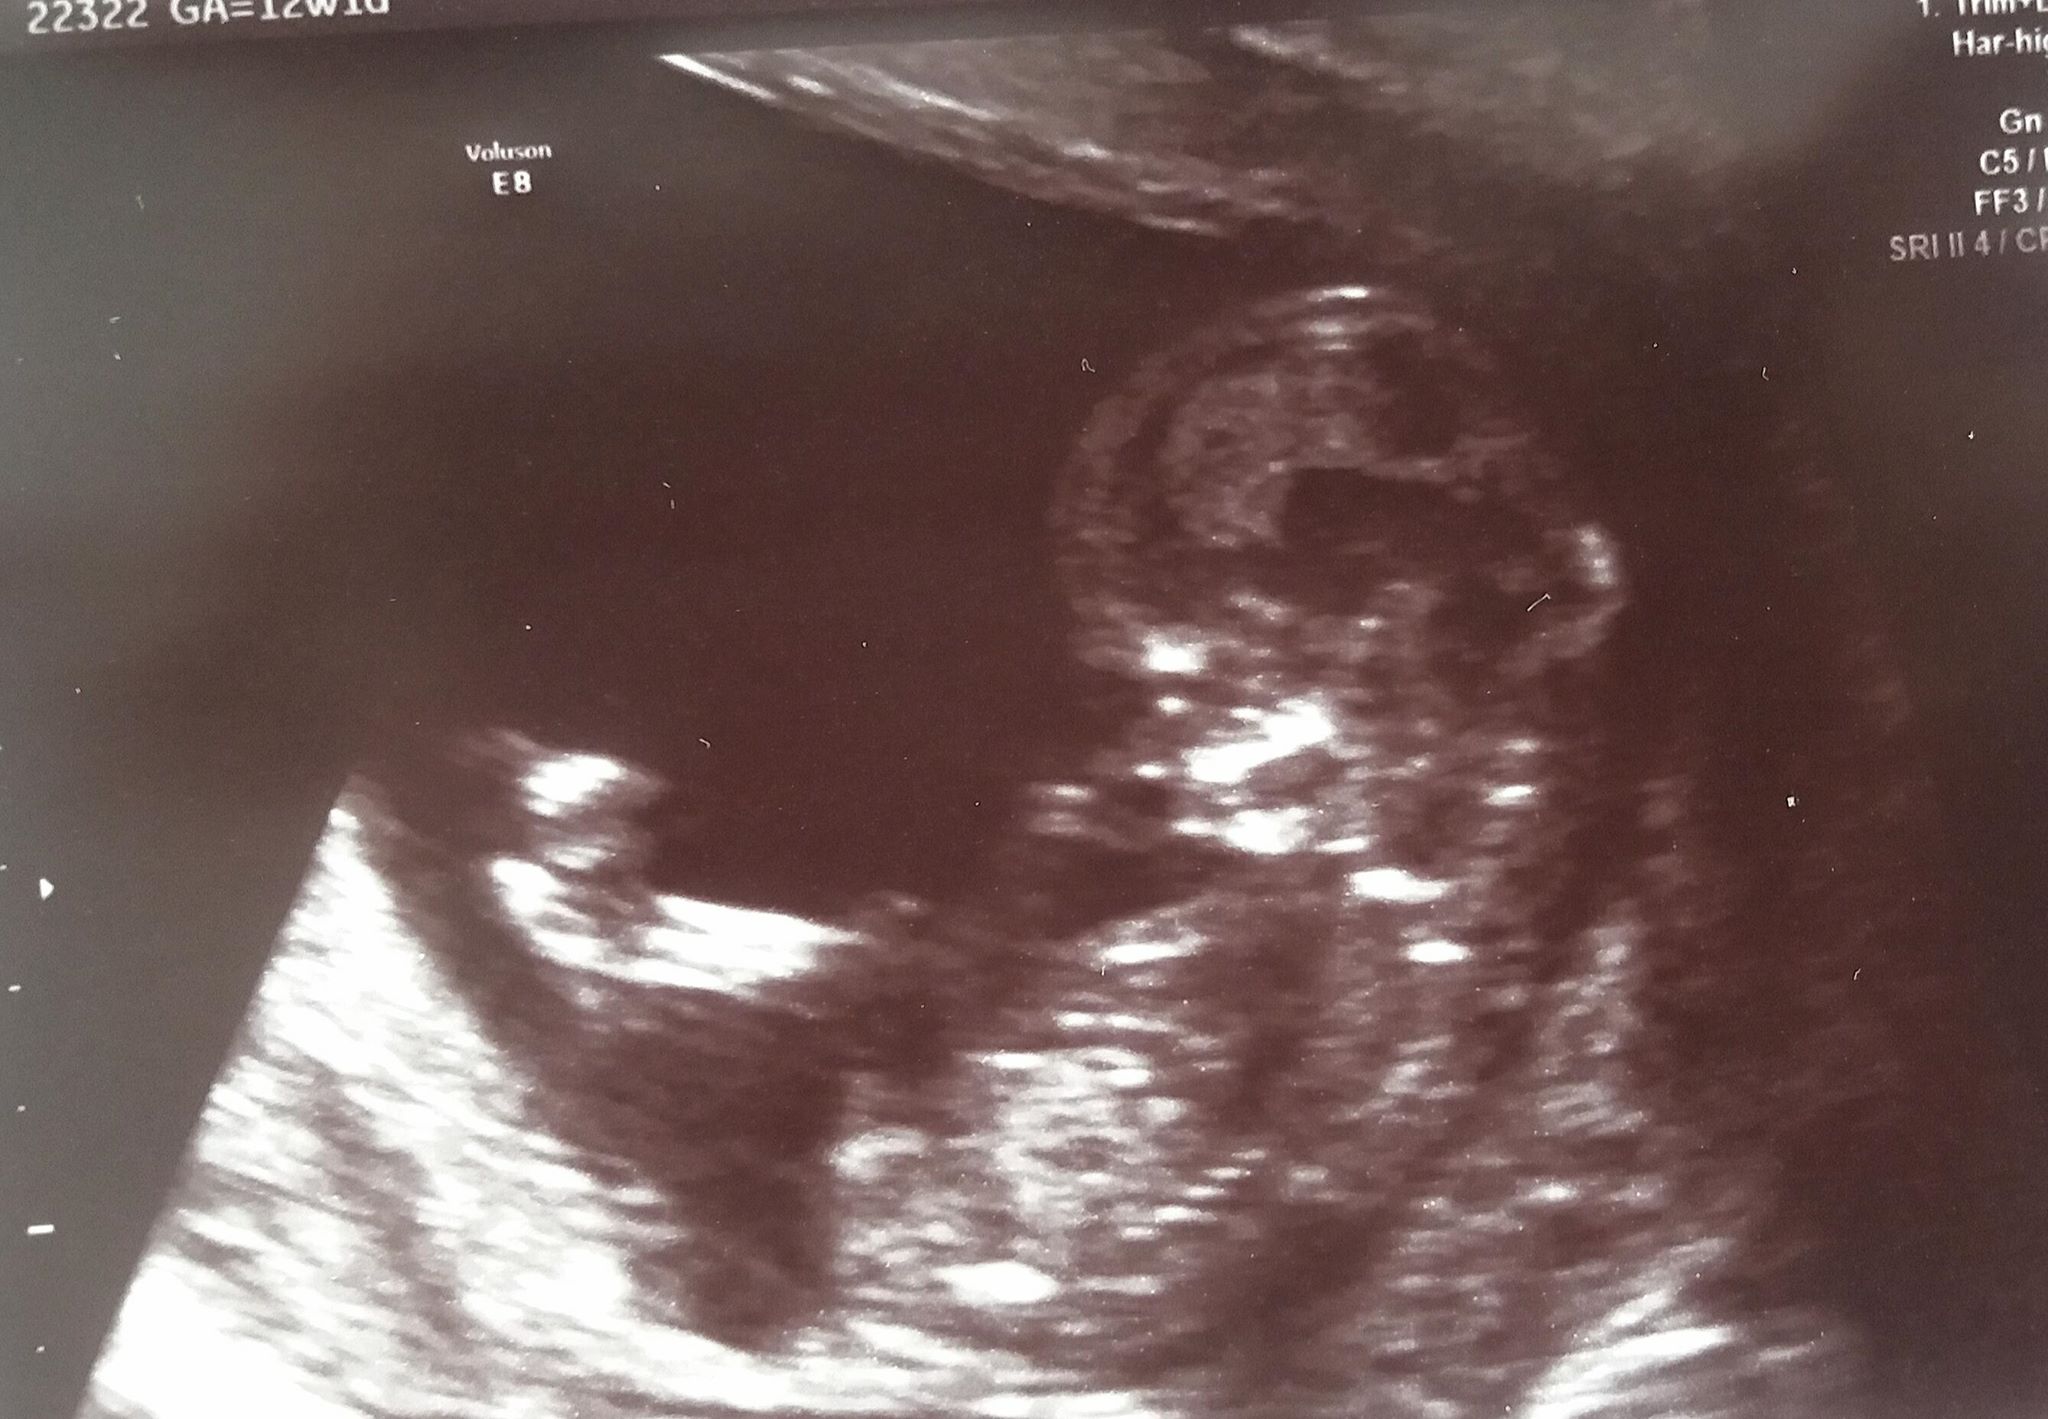

Widze nosek Wy tez prawda Zobacz załącznik 865325

Widać nosek jak byk :) i usteczka widać. Nie rycz, bo na pewno wszystko jest ok!

Ale to chyba te 2 kropeczki są te kosteczki

Ale wymyślasz [emoji23][emoji23][emoji23][emoji23] piekna wyrazna dzidzia[emoji173]